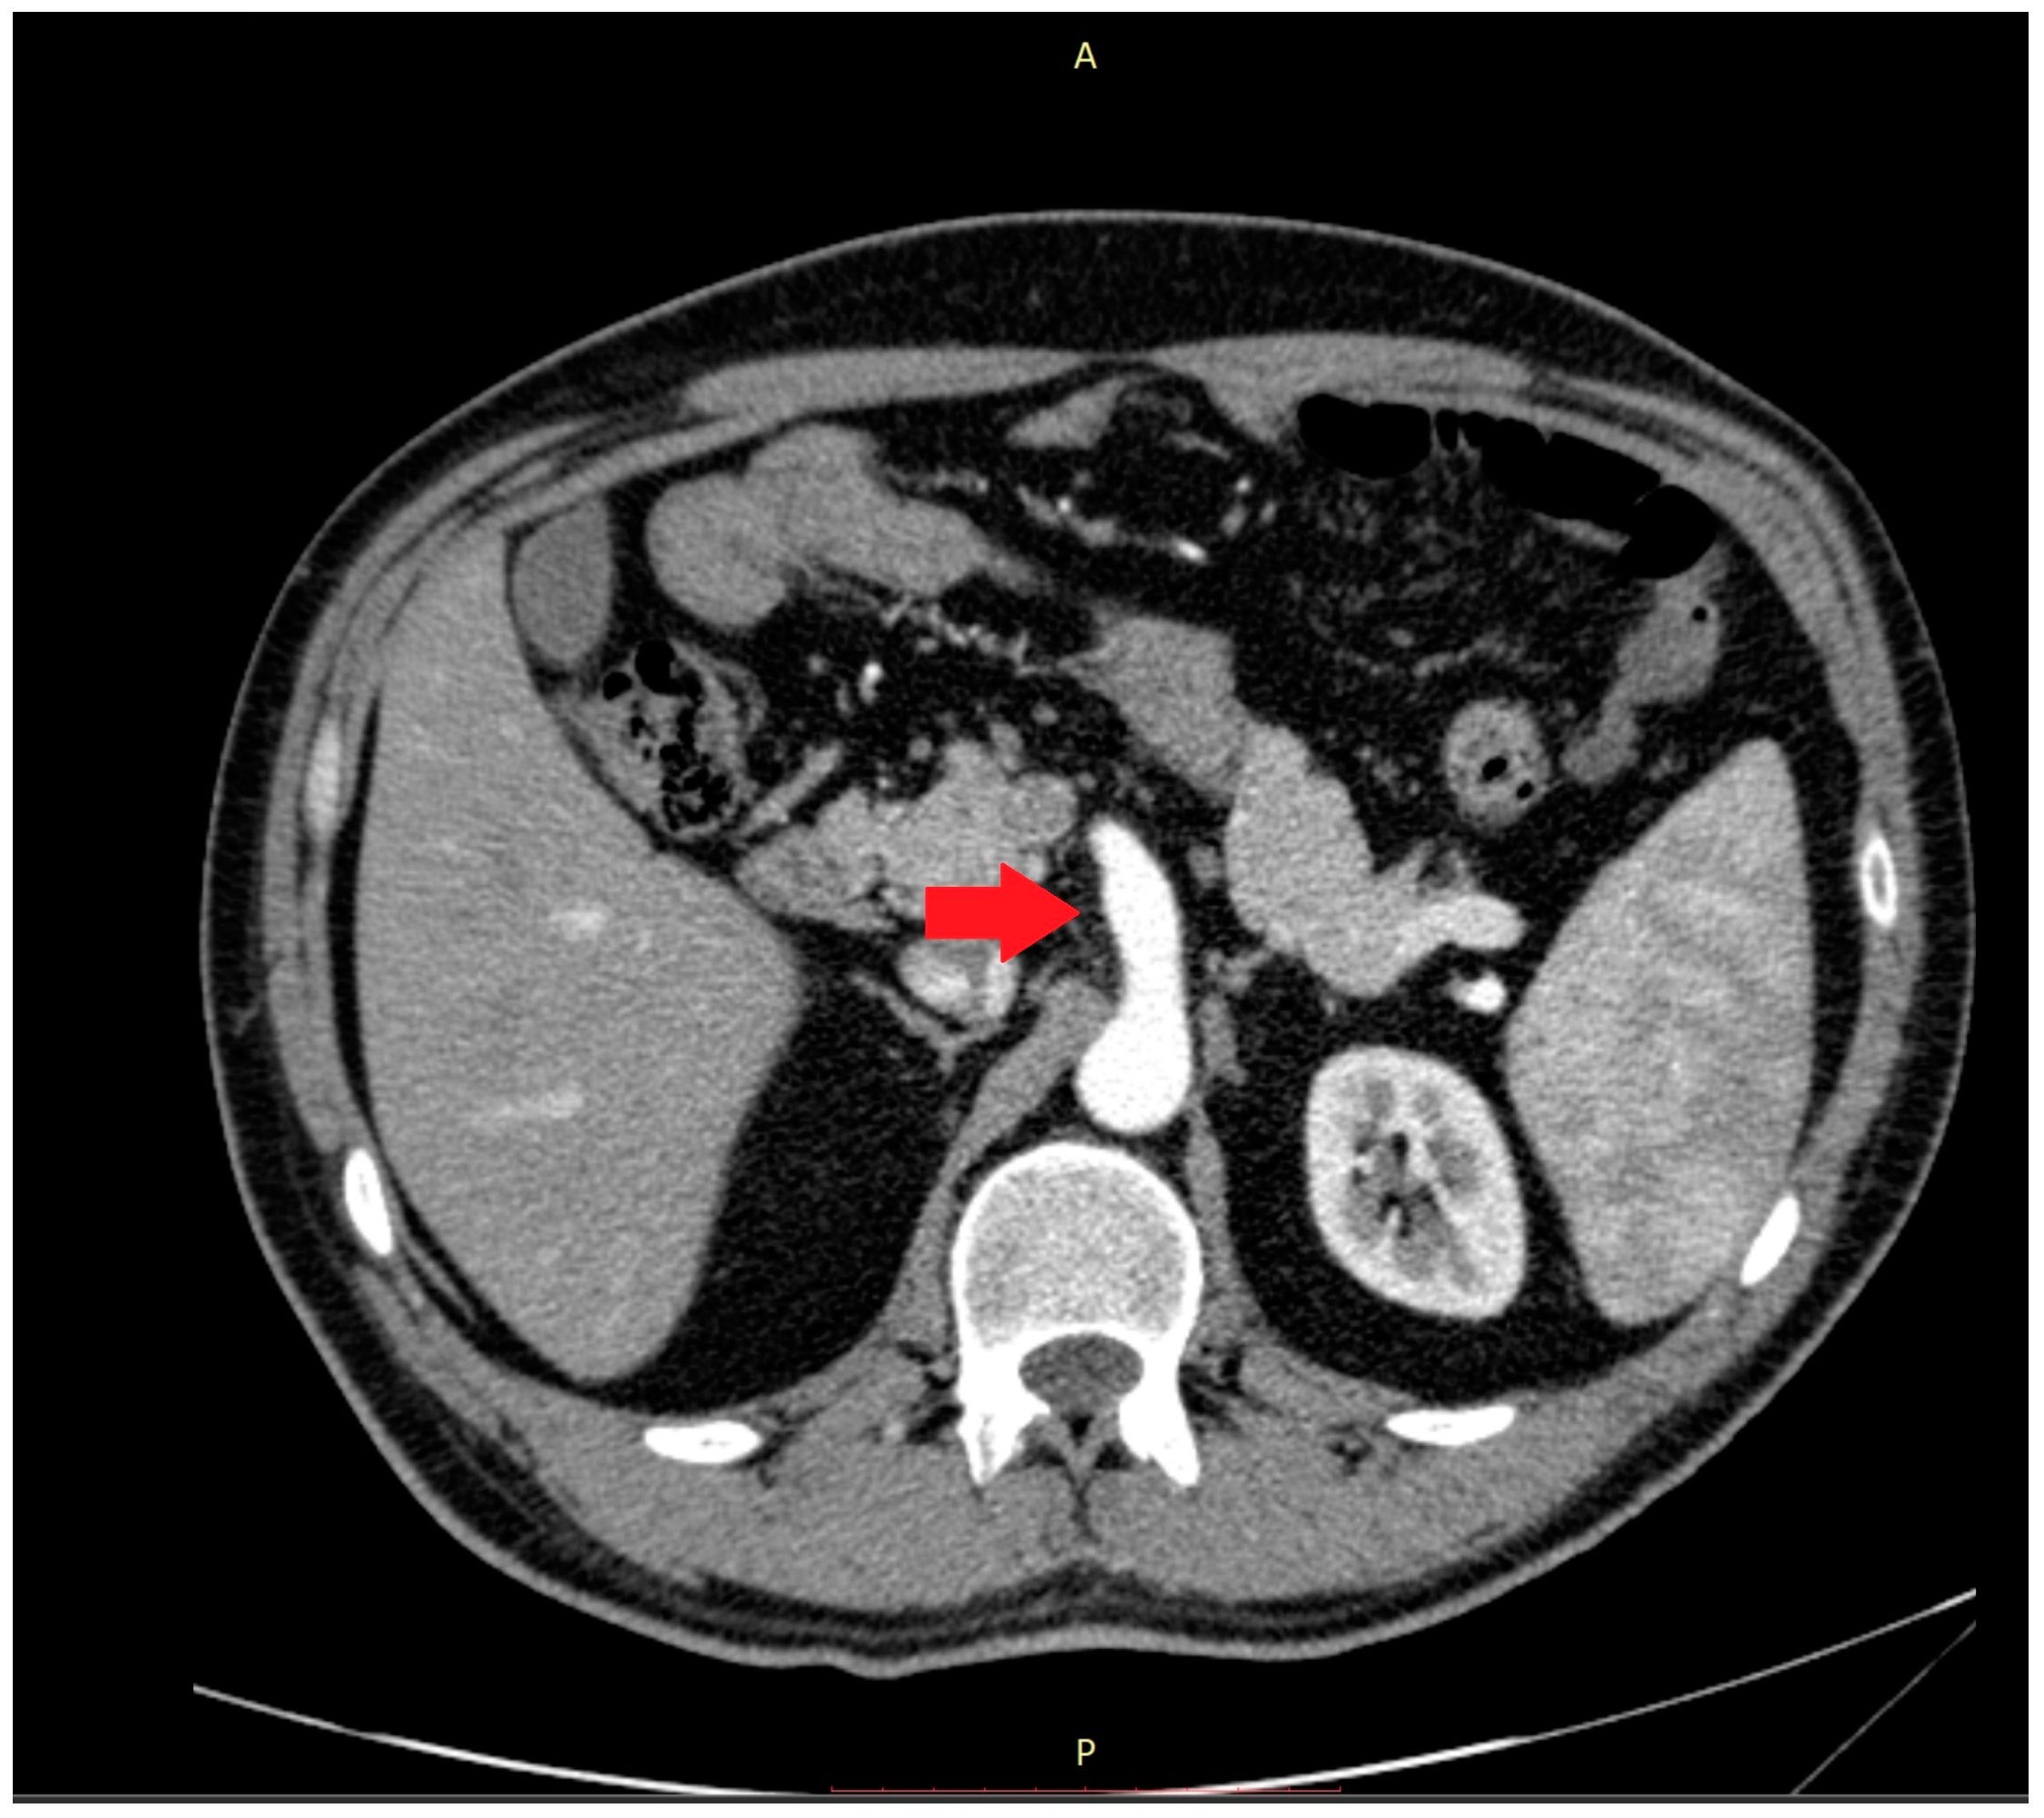

Abnormalities were also present in the CT scan with and without contrast medium (Figure 2 and Figure 3).

Figure 2.

The computer tomography scan confirmed the agenesis of the left hepatic lobe, splenomegaly, and an enlarged celiac-mesenteric trunk (red arrow).

Figure 3.

In the 3D reconstruction of CT scan images, the enlarged celiac-mesenteric trunk can be observed indicated by a black arrow.